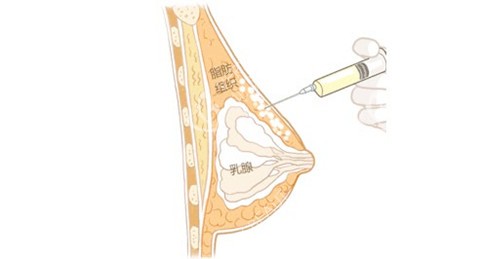

面诊时,齐云香医生拿着我的三维CT片耐心解释:“奥美定已渗透到乳腺后间隙和胸大肌层,像沙子混进水泥,必须分层剥离。

医生团队先通过CT定位奥美定分布,接着在乳晕边缘开2厘米切口。

当3D内窥镜探入时,我听到医生轻声说:“看,这些白色颗粒就是奥美定,像散落的珍珠。”他们用清奥剥离液软化粘连组织,再用小创口抽吸仪逐层清理。

较惊险的是清除胸大肌层的残留——奥美定已包裹在肌肉纤维间,稍有不慎就会损伤神经。